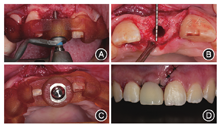

鉴于11根尖区骨质破坏范围较大,无法提供即刻种植所需的初期稳定性,故拔除残根后行位点保存。彻底清理牙槽窝,生理盐水和双氧水反复冲洗,拔牙窝内放置足量骨替代材料(Bio-Oss骨粉,Geistlich,Wolhusen,瑞士),取上颌左侧前磨牙腭侧角化上皮腭黏膜半厚瓣,覆盖并关闭拔牙创口,纤维带粘接桥临时修复11(图3)。

像;D:腭侧术区2周后复查愈合良好

像;D:腭侧术区2周后复查愈合良好位点保存术后6个月复查,锥形束CT示骨量充足,根尖区低密度影已消失;口内见11唇侧牙龈曲线初步成形(图4)。选择窄颈种植体(ITI Straumann BL 3.3 mm×12.0 mm,士卓曼,瑞士)以最大限度减少种植体占位,余留更多成骨空间。设计唇侧保留3.0 mm,腭侧保留1.0 mm骨板厚度,植入深度位于唇侧骨缘下1.0 mm,中央螺丝从舌侧穿出的牙支持式全程种植导板(图5)。

面像可见卵圆窝初步成形全程种植导板引导下行11牙位定点,逐级备洞,植入窄颈种植体。术中可见11种植位点新生骨表面留有少量颗粒状骨替代材料,内部成骨良好,种植体植入扭矩达35 N·cm,满足即刻修复需求(图6)。术后锥形束CT示种植体植入位置与设计基本一致(图7),植入与设计的颈部和根部误差分别为0.47和0.45 mm。